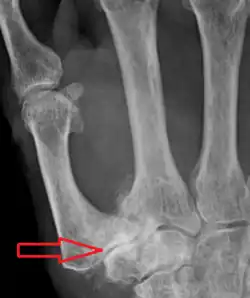

Classification

TMC OA severity was classified by Eaton and Littler which can be simplified as follows:[21][22]

Stage 1:

- slight widening of the joint space

- < 1/3 subluxation of the joint (in any projection)

Stage 2:

- Osteophytes, < 2 mm in diameter, are present. (usually adjacent to the volar or dorsal facets of the trapezium)

Stage 3:

- Osteophytes, > 2 mm in diameter, are present (usually adjacent to the volar and dorsal facets of the trapezium)

- Slight joint space narrowing

Stage 4:

- Narrow joint space

- Concomitant scaphotrapezial arthritis

A simpler classification is no arthritis, some arthritis, and severe arthritis.[23] This simpler classification system omits the potentially contradictory details of the Eaton/Littler classification and keeps scaphotrapezial arthrosis separate.